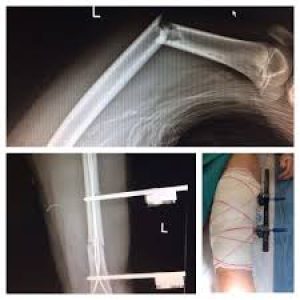

descarga femur